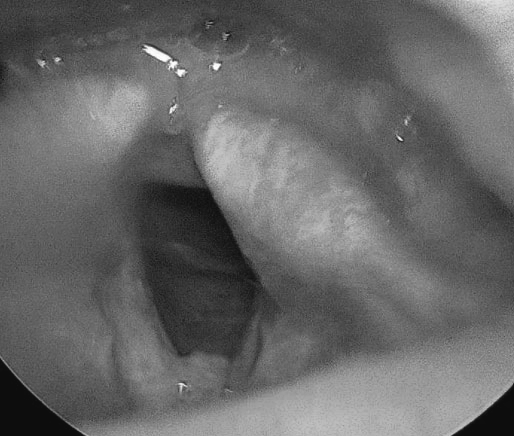

자궁경부 이형성증, 레이저로 HPV 바이러스 소멸이 될까?

자궁경부 이형성증, 레이저로 HPV 바이러스 소멸이 될까? 안녕하세요. 오늘도 HPV에 대한 질환 정보...